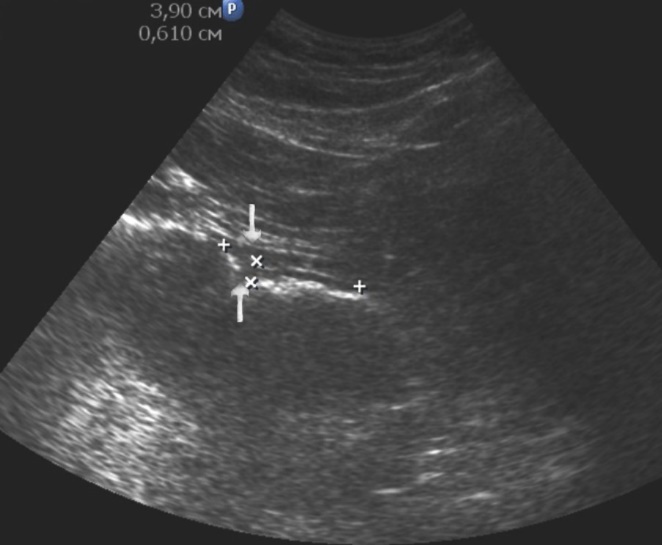

Distal gastric cancer was observed in 24 (39,3%) cases and contributed to the development of pyloric stenosis: in 6 (9,8%) cases it was compensated, in 18 (29,5%) – was sub compensated. The layers of the wall were not differentiated in all patients with sub compensated pyloric stenosis. In the case of compensated pyloric stenosis, the thickness of the affected area was 10,2±2,9mm, the length was 27,1±6,2mm, the diameter of the pylorus was 8,3±0,8mm (Figure 14). Among patients with sub compensated pyloric stenosis, the thickness of the stomach wall was 19,8±4,1mm, the length was 43,6±4,5mm, the pyloric diameter was 4,3±1,1mm (Figure 15).

Figure 14.Gastric carcinomas of diffuse infiltrative form in the atrium of T2 stage. Compensated pyloric stenos. On an empty stomach in the cavity of the stomach is determined an a small amount of fluid. The diameter of the pyloric canal more than 7 mm.